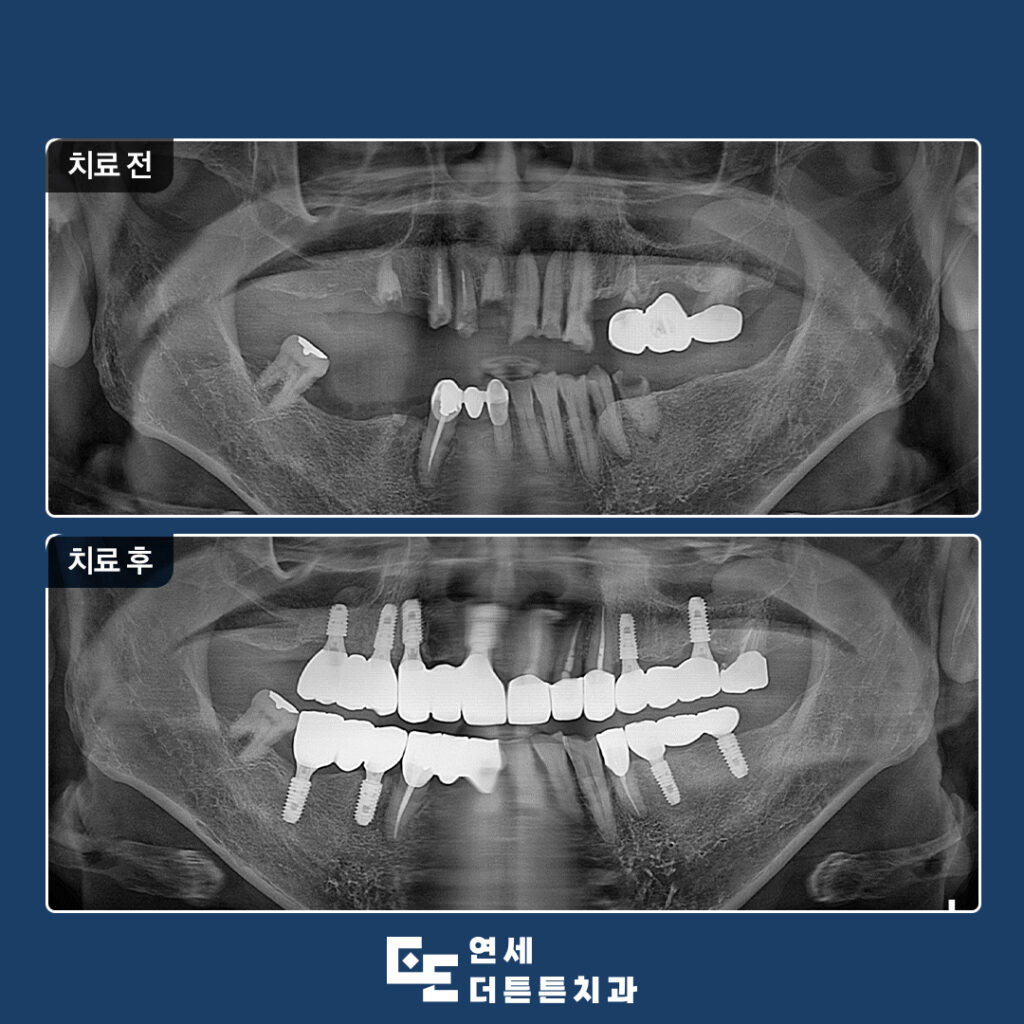

환자분께서는 구강 내 어금니 부위를 거의 상실하신 채로, 남아 있는 치아들도 부러져 제 기능을 하지 못해 치료 상담을 위해 방학역치과에 내원해 주셨습니다.

다수의 치아가 손상되거나 상실된 상태로 내원하였으며, 잔존 치아 또한 심한 우식과 변색, 구조적 약화가 동반된 상태였으므로 일부 치아는 보존이 어려운 상태였기 때문에 발치를 진행하였고, 남아 있는 치아 중 사용 가능한 치아는 신경치료 및 보강을 통해 최대한 활용하는 방향으로 치료를 계획하였습니다.

먼저 예후가 좋지 않은 치아들을 발치하고 결손 부위에는 임플란트를 식립하여 기능적인 지지 기반을 형성하였으며 최종 보철물이 들어가기 전 기간동안 사용하실 수 있는 임시틀니를 제작해 드렸습니다. 임플란트가 뼈에 제대로 붙기까지는 시간이 필요하며, 일반적으로 상악은 약 6개월, 하악은 약 4개월이 소요되어 그 기간동안 사용하시며, 최종 보철물에 대한 전반적인 상담도 충분히 진행할 수 있도록 하였습니다.

이후 기존 치아와의 조화를 고려하여 보철 치료를 진행하였습니다. 치료 과정에서는 단순히 치아를 대체하는 것에 그치지 않고, 교합의 균형과 저작 기능 회복, 그리고 자연스러운 외관까지 함께 고려하였습니다. 특히 전치부의 경우 심미적인 요소가 중요한 부위이기 때문에 치아의 형태와 색상, 배열을 세밀하게 조정하여 전체적인 인상이 자연스럽게 개선될 수 있도록 하였습니다.

또한 잇몸 상태 역시 치료 결과에 큰 영향을 미치기 때문에 염증 관리와 위생 상태 개선을 병행하면서 치료를 진행하였습니다. 단계별 치료를 통해 점진적으로 구강 환경을 안정화시키고 최종적으로 기능과 심미를 모두 만족할 수 있는 상태로 마무리하였습니다.